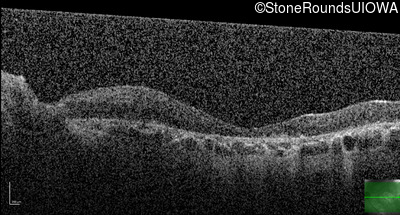

Optical Coherence Tomography - Left - 1/400 sc

Exemplar / OCT Stack